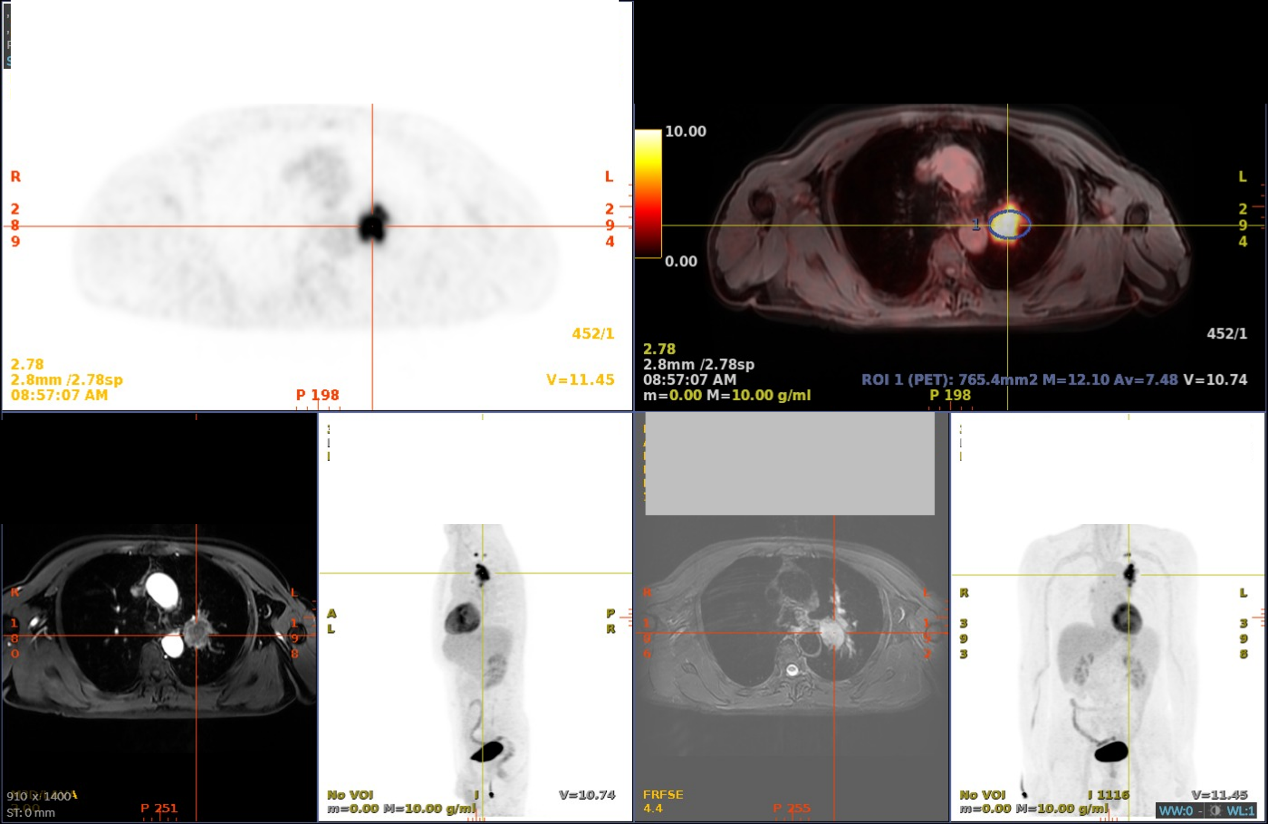

新辅助治疗:2022-08-28、2022-09-20行2周期术前新辅助治疗:紫杉醇聚合物胶束 (390mg 静滴 d1)+顺铂(100mg 静滴 d1)+舒格利单抗(1200mg 静滴 d1)

2周期后疗效评价:PR

图3. 新辅助治疗前(2022-08-22,上)后(2022-10-11,下)对比